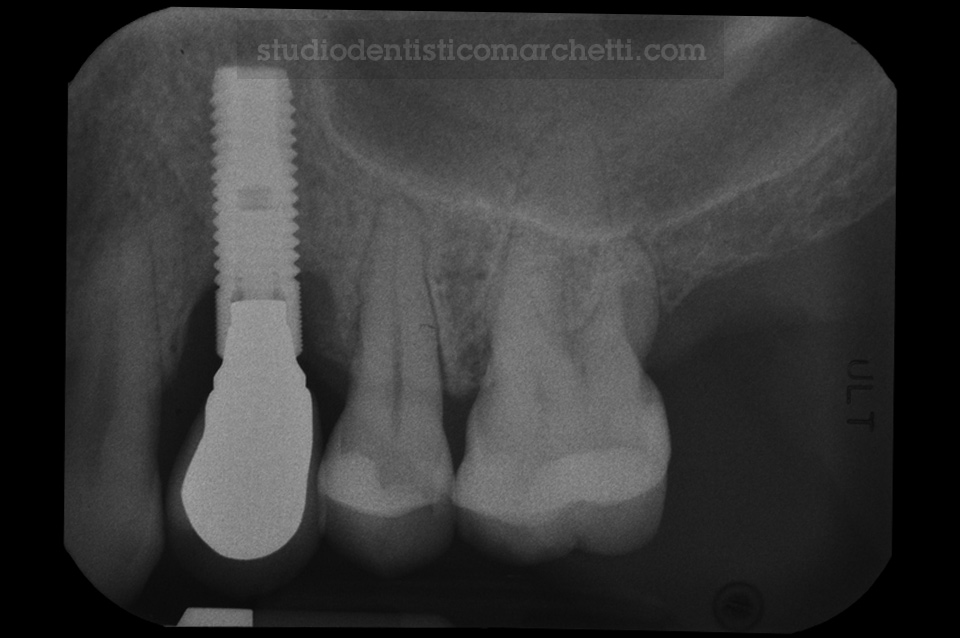

Implantologia e Trattamento delle Preimplantiti

Trattamento della Perimplantite

Implantologia e Trattamento delle Preimplantiti / Odontoiatria Protesica

Protesi Fissa su Dente Naturale e su Impianti